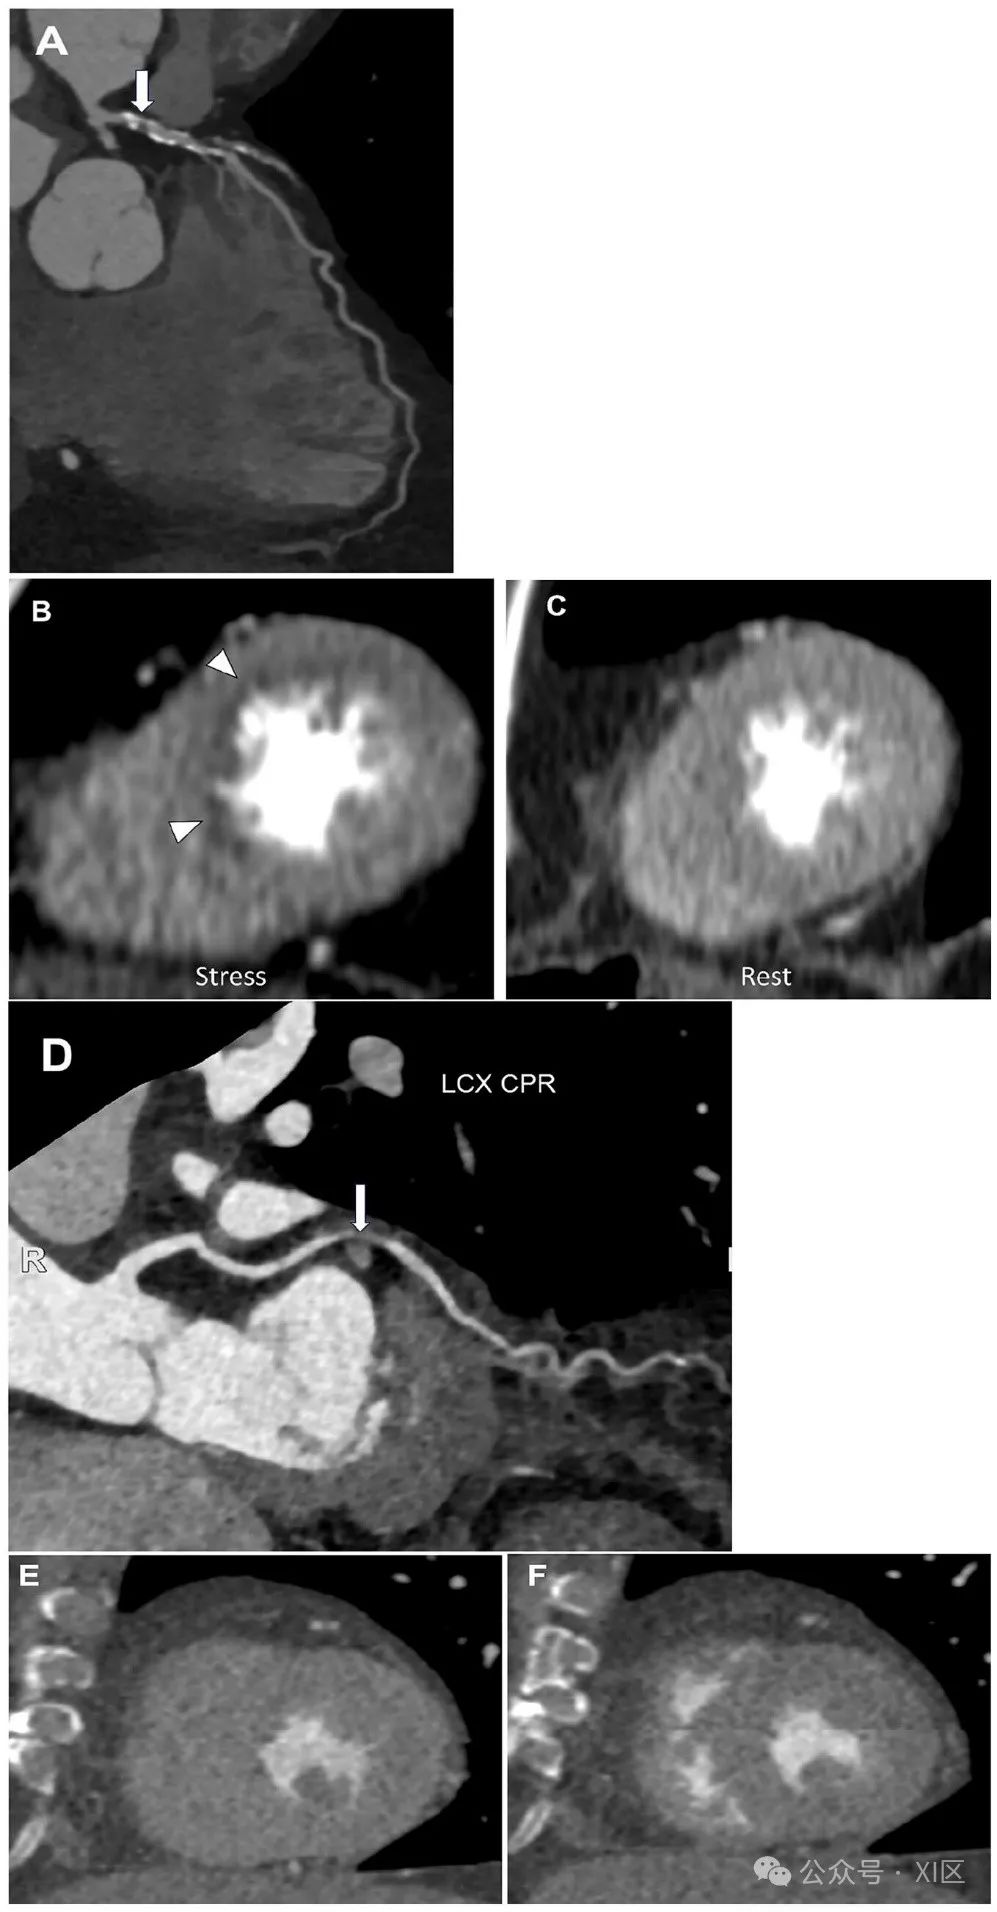

(A) 左前降支近端严重狭窄(CAD-RADS 4A,箭头所示),(B) 在负荷影像中可见左前降支供血区域可逆的灌注缺损,© 但在静息影像中未见灌注缺损,提示心肌缺血。(D) 左回旋支中段严重狭窄(CAD-RADS 4A,箭头所示),(E) 在负荷影像中未见灌注缺损,(F) 静息影像中也未见灌注缺损。